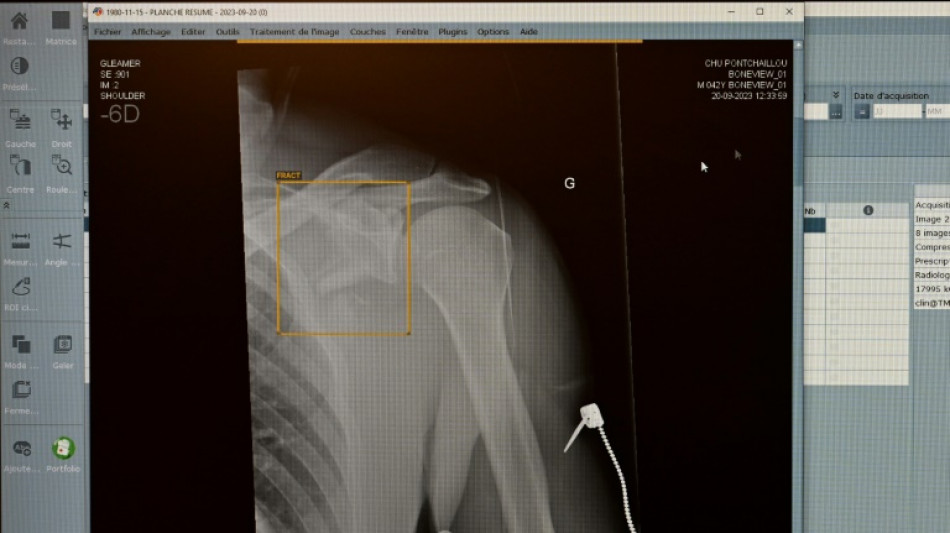

Zweitmeinung von KI bei Gesundheitsproblemen: Für jeden Zweiten vorstellbar

Jeder Zweite kann sich vorstellen, eine Anwendung mit Künstlicher Intelligenz (KI) bei Gesundheitsproblemen um eine Zweitmeinung zu ersuchen. Nach einer am Dienstag in Berlin veröffentlichten Umfrage des Digitalverbandes Bitkom ist das für 51 Prozent der Teilnehmenden eine Option.

Fast die Hälfte der Befragten (47 Prozent) traut einer KI laut Befragung in bestimmten Fällen sogar bessere Diagnosen zu als Menschen. Auf der Suche nach Informationen zu Diagnosen, Nebenwirkungen verordneter Arzneimittel oder zur Abklärung von Symptomen haben sich demnach sechs Prozent schon einmal bei einer KI bedient - etwa über Symptomchecker-Apps oder Chatbots wie ChatGPT.

Viele Menschen haben jedoch auch Sorgen. Einem Drittel (35 Prozent) macht der Einsatz von KI in der Medizin Angst. Mehr als drei Viertel (79 Prozent) der Deutschen sprechen sich dafür aus, den Einsatz Künstlicher Intelligenz in der Medizin streng zu regulieren. Im Auftrag von Bitkom wurden zwischen Mitte Mai und Anfang Juni 1140 Menschen ab 16 Jahren telefonisch befragt.